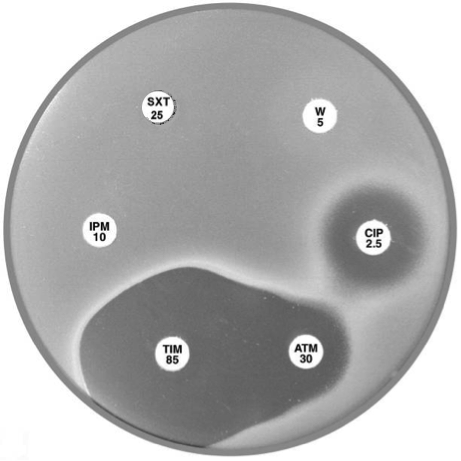

Plate 12.14.B Pseudomonas aeruginosa producing a metallo β-lactamase (carbapenemase) Showing the inhibition of the carbapenemase by EDTA. |